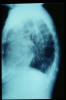

TBC pulmonar antigua